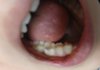

이거 충치임? 나 치과가야돼??